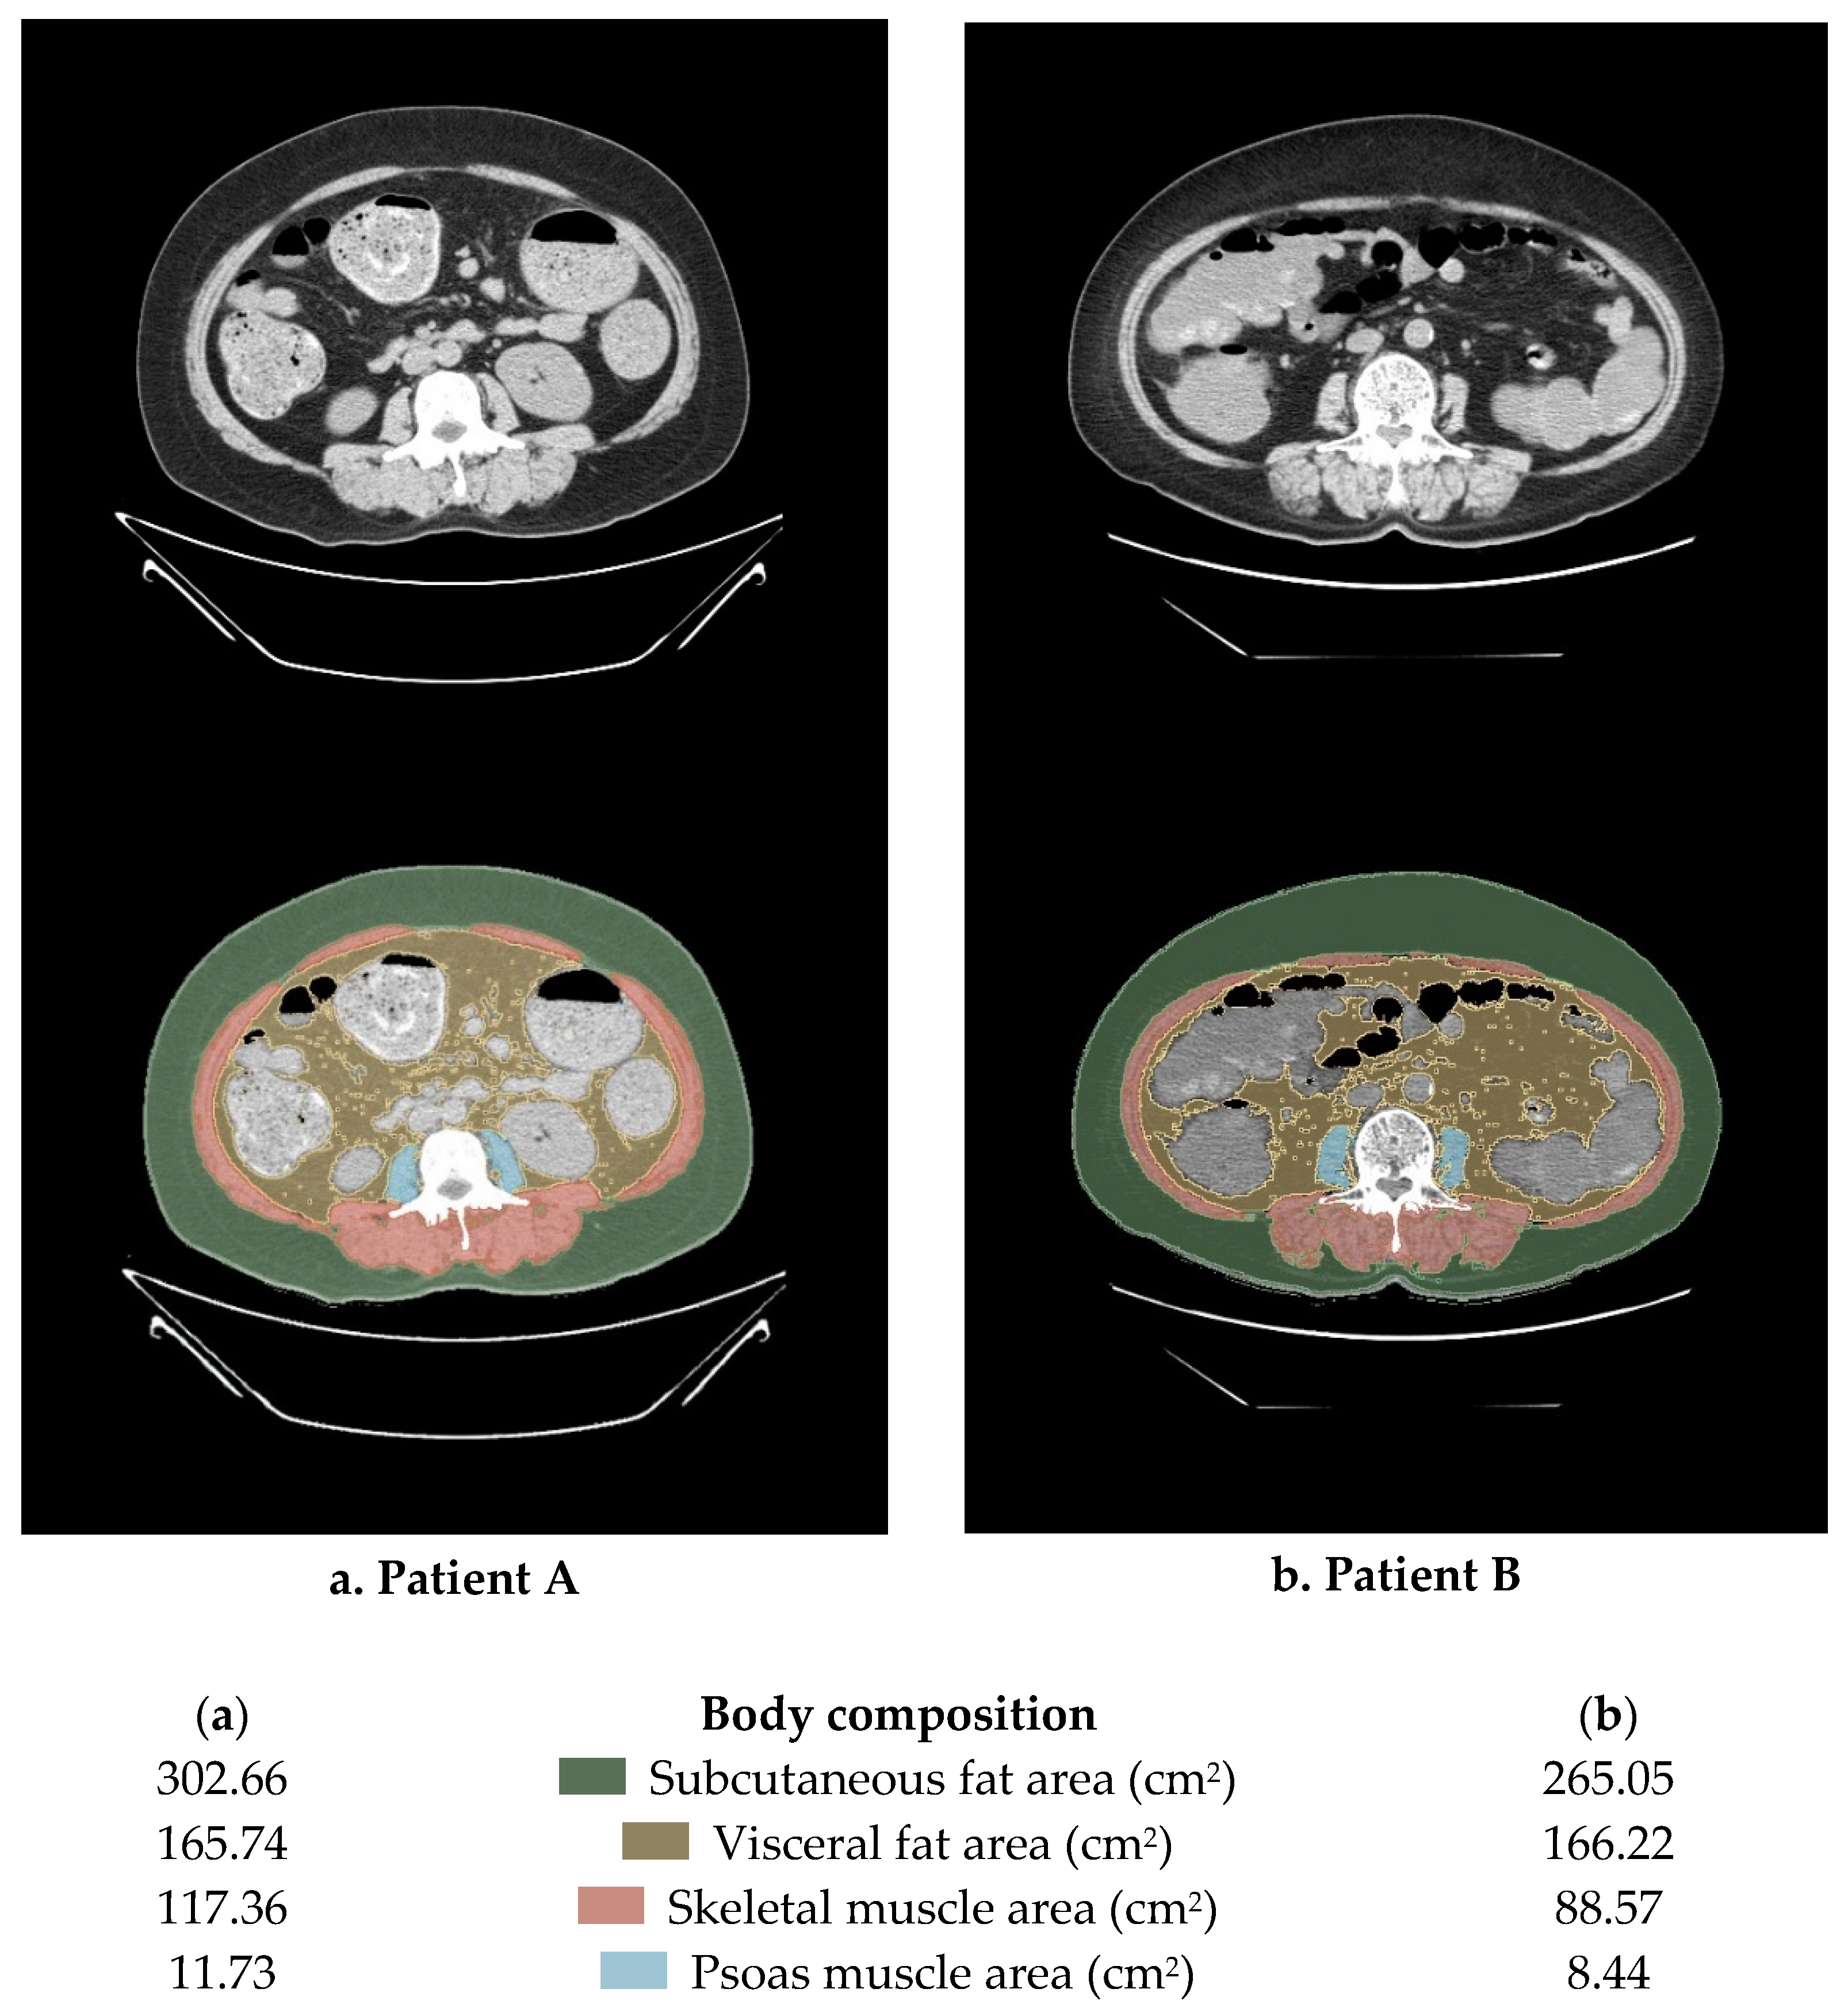

2.4. Measures of Body Composition